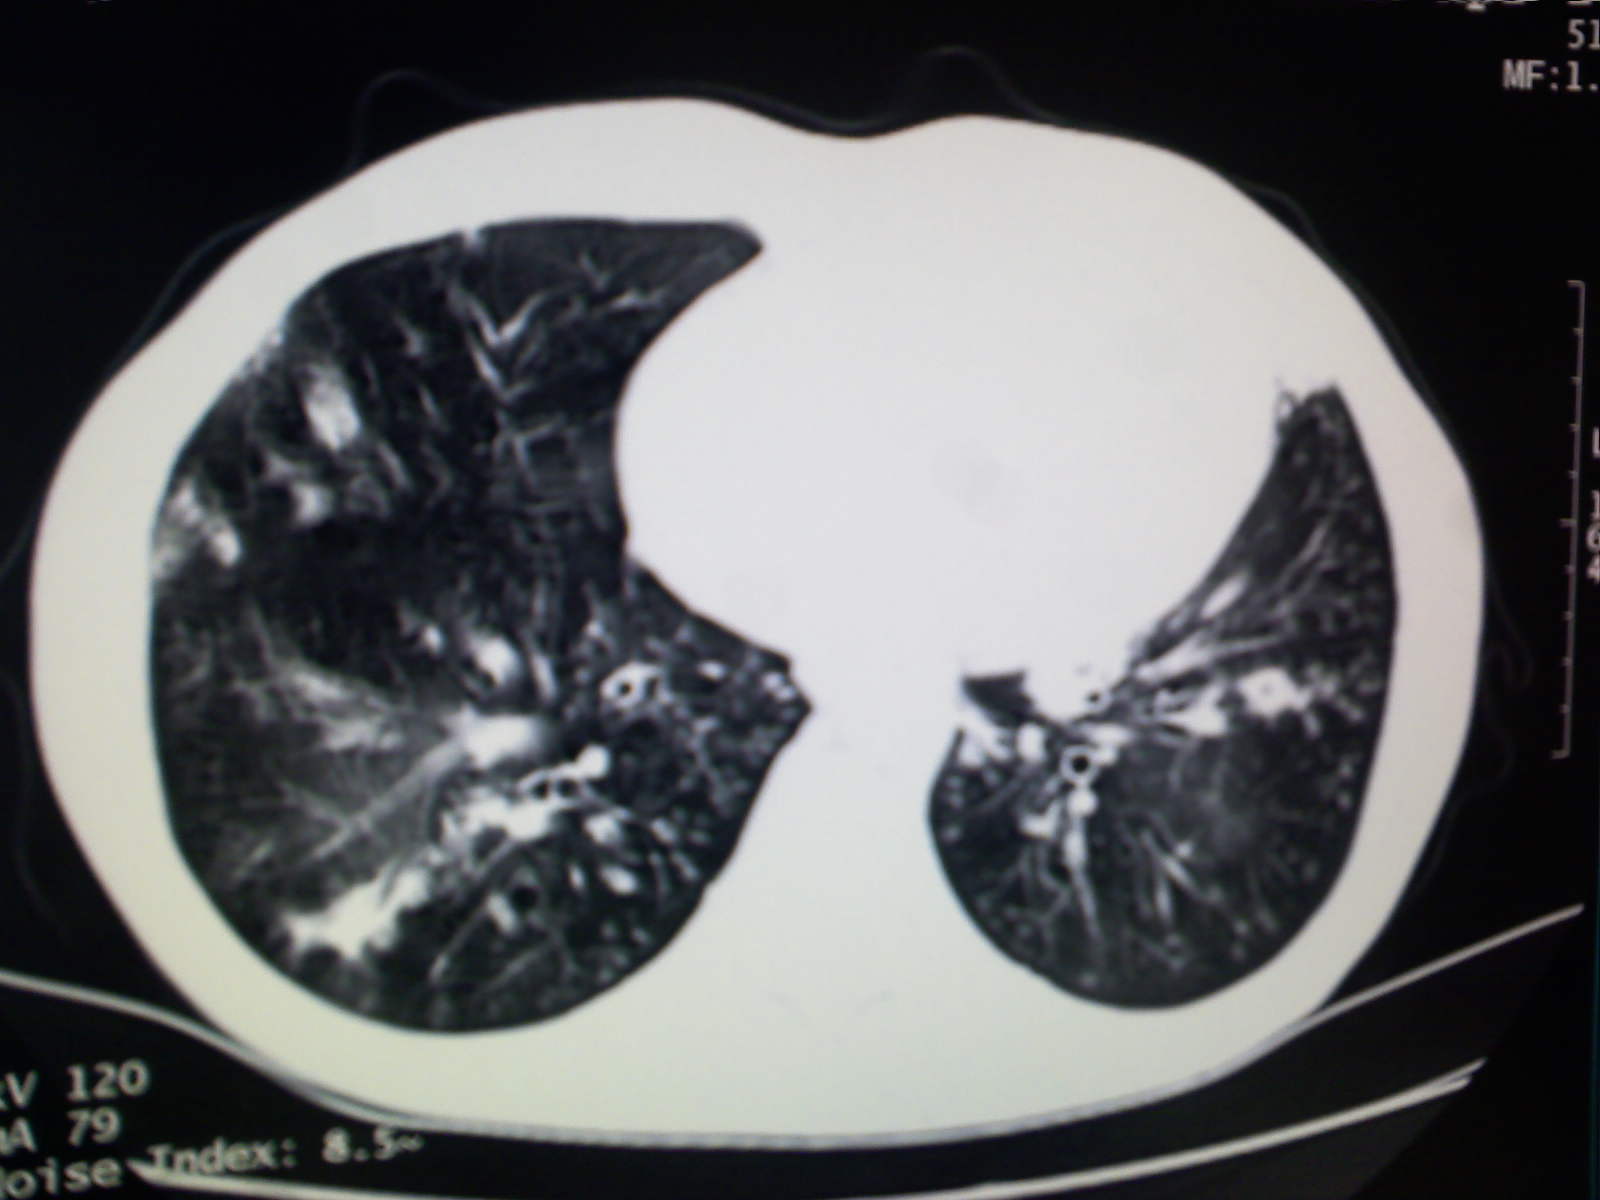

以下是引用卜一在2009-4-11 15:50:00的发言:[br]双肺继发性肺结核伴空洞形成,不排除合并霉菌感染!(病灶呈多形态 多特征 散在分布)。另:合并支气管扩张征伴感染!

以下是引用主力军在2009-4-11 15:55:00的发言:[br]两肺继发性肺结核可能性大。

以下是引用康鹏在2009-4-11 16:30:00的发言:[br]双肺继发性肺结核伴空洞形成合并感染[br]支气管扩张合并感染